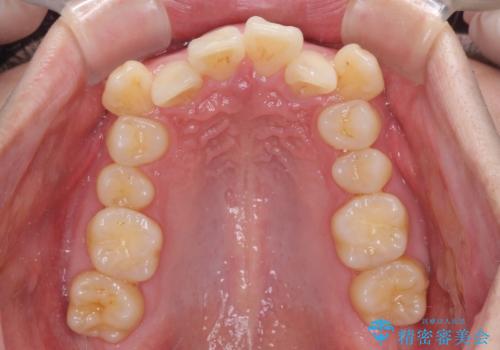

- 八重歯を気にして来院された患者様です。

顕著な上顎の八重歯とディープバイトであったため、上顎の左右第一小臼歯を抜歯することとしました。

犬歯歯根の位置や奥歯の咬み合わせから、ワイヤー装置での治療を強くおすすめいたしましたが、ご本人の強い希望により、妥協的な仕上がりとなることを了解いただき、インビザラインにて矯正治療を行うこととしました。

インビザライン単体で、左右ともに移動の難しい位置に歯根のある犬歯を整えるのは困難と判断し、補助装置を併用することとしました。